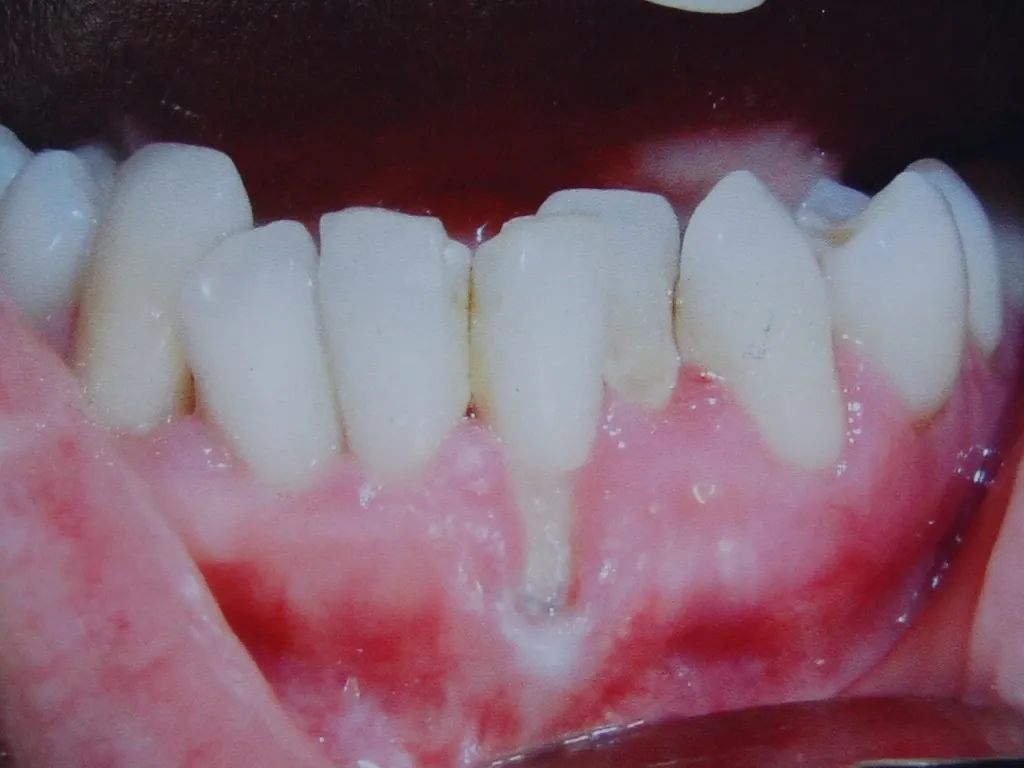

Guided Tissue Regeneration with Bone Graft & Growth Factors to Save teeth